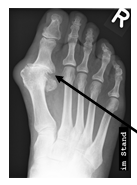

Hallux valgus et rigidus (Zehenballen mit Arthrose)

Diese Fehlstellung im Sinne eines Hallux valgus ist kombiniert mit einer Arthrose des Großzehengrundgelenkes. Genauso wie bei Arthrose ohne Fehlstellung sollte zunächst versucht werden, die Beschwerden mit einer Anpassung des Schuhs und mit Einlagen zu lindern. Wenn hier keine ausreiche

Auf dem Röntgenbild zeigt sich die fortgeschrittene Arthrose des Großzehengrundgelenkes. Der Knorpel ist vollkommen zerstört (Pfeil). Es reibt Knochen auf Knochen, was die Schmerzen verursacht.